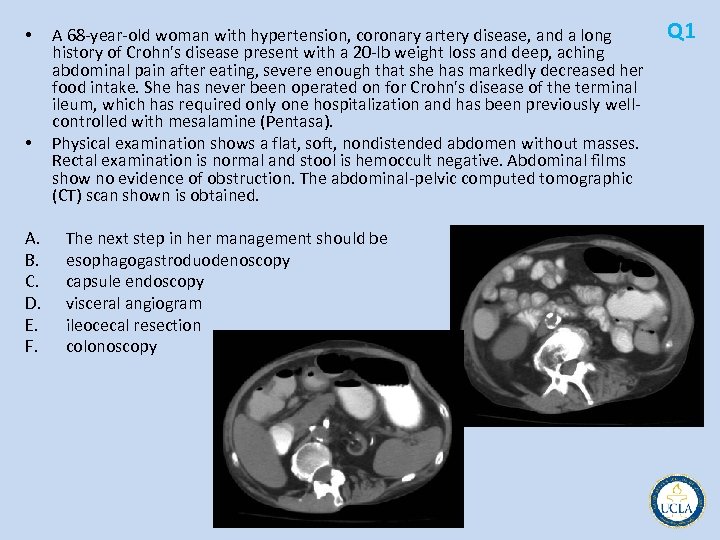

Q 1